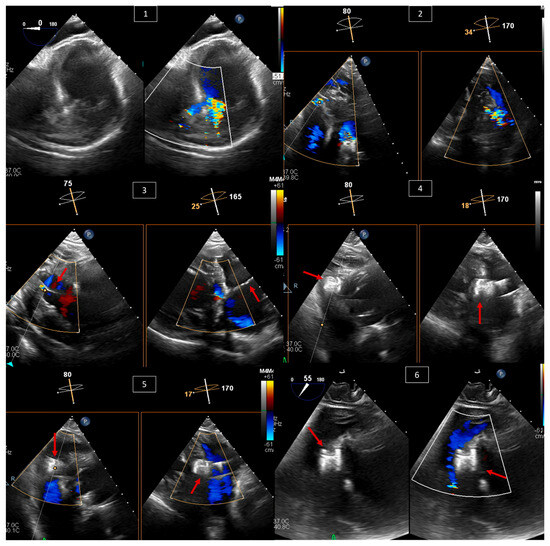

洋書 Echocardiography in Congenital Heart Dis Buy Echocardiography in Pediatric and Congenital Heartの詳細情報

Buy Echocardiography in Pediatric and Congenital Heart。Echocardiography in Adult Congenital Heart Disease。Echocardiography for Congenital Heart Disease: Fundamental。 現在、1名がこの商品を検討中です

Highlights of Transesophageal Echocardiography During

Highlights of Transesophageal Echocardiography During

「EchocardiographyinCongenitalHeartDisease:ExpertConsult:OnlineandPrint」

EchocardiographyinPediatricandAdultCongenitalHeartDisease-avolumeintheexcitingnewPracticalEchocardiographySerieseditedbyDr.Cather…

EchocardiographyinPediatricandAdultCongenitalHeartDisease-avolumeintheexcitingnewPracticalEchocardiographySerieseditedbyDr.Cather…